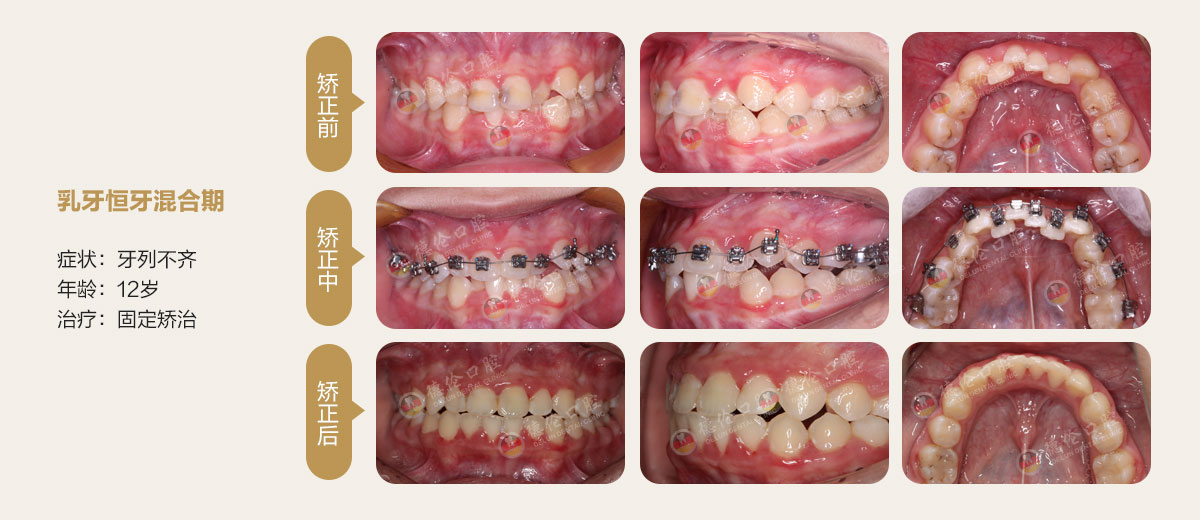

替牙期阶段(8-12岁)(女孩8-10岁 男孩9-12岁)

这个时期是孩子生长发育的青春前期,牙齿矫正治疗可以充分利用颌骨生长潜能,通过促进或抑制颌骨的生长而达到治疗目的,对改善孩子的面形颌功能更有利。

适应证:主要矫正青少年常见的错颌畸形

佩戴时间:不能自行摘戴,矫正力较为持续